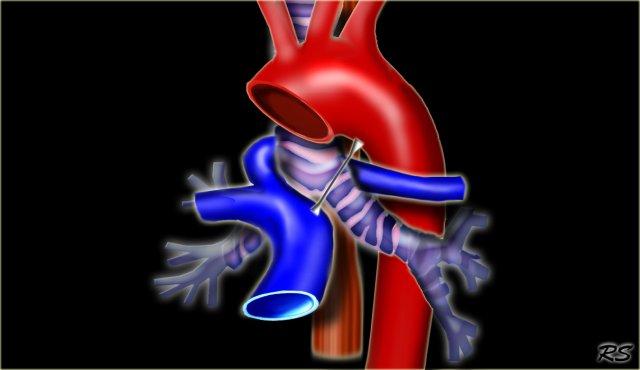

The Right Aortic Arch with an aberrant left subclavian is an obstructing arch anomaly.

The first branch of the aorta is the left common carotid, followed by the right subclavian artery and the left common carotid.

This also is a true ring.

The ligamentum ductus arteriosus between the arch at the level of the left subclavian artery and the left pumonary artery completes the ring.

If this ligament is very short, there will be a lot of compression.

On the left a patient with a right arch with an aberrant left subclavian (indicated by the yellow arrow).